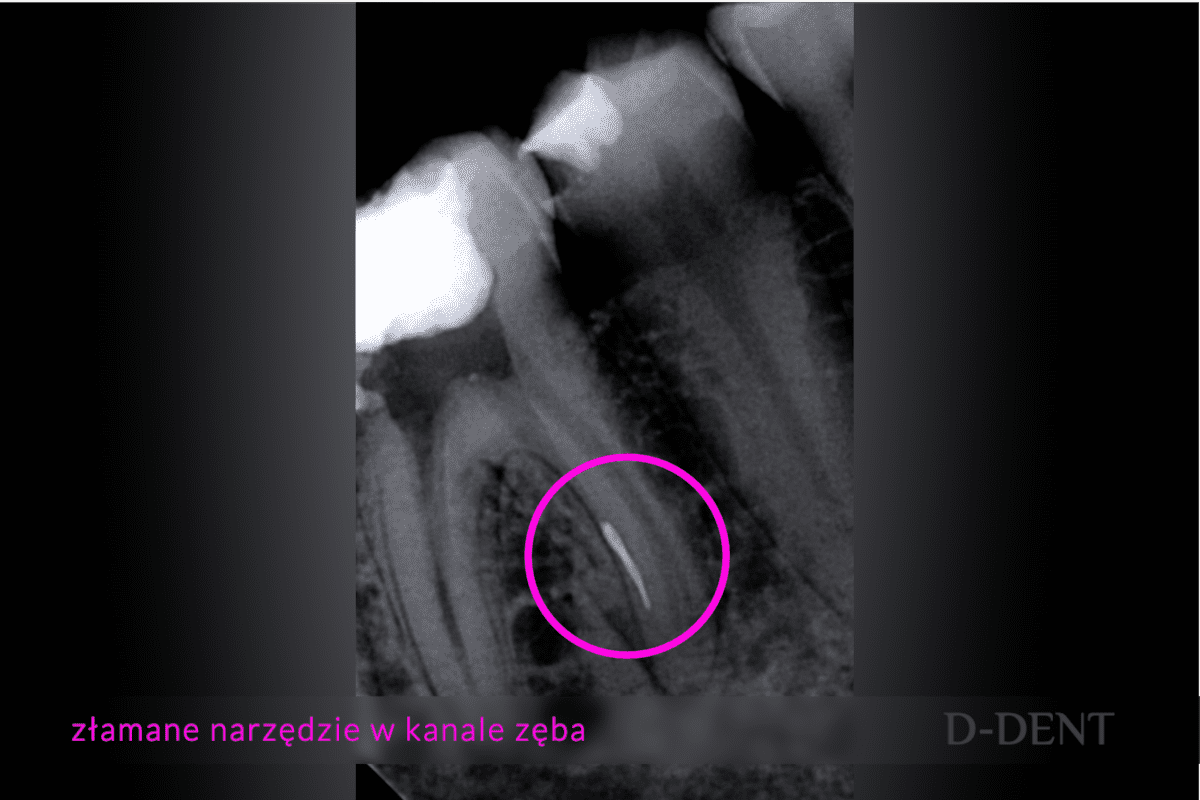

W pierwszej kolejności zrobiliśmy zdjęcie rentgenowskie, aby ocenić na jakim etapie leczenia jest Pacjent i okazało się, że w jednym z kanałów zęba, pozostawiono fragment narzędzia endodontycznego. Najprawdopodobniej doszło do tego w trakcie próby udrażniania kanału. Narzędzie złamało się, co spowodowało trudności w usunięciu martwej, już zgorzelinowej tkanki z kanału korzeniowego. Te pozostawione martwe tkanki mogły doprowadzić do powstania stanu zapalnego w tkankach około wierzchołkowych. Na szczęście, nie doszło do tak poważnego powikłania i sprawę opanowaliśmy podczas jednej wizyty, to znaczy usunęliśmy złamane narzędzie bez żadnych powikłań.

Zdjęcia RTG obrazujące złamane narzędzie w kanale zęba oraz stan po usunięciu narzędzia i wyleczeniu kanałowym - przypadek opisany w artykule blogowym; fot.:lek. dent. Aliaksandr Pshebylinski  - leczenie kanałowe Sopot, D-DENT Centrum Nowoczesnej Stomatologii

To zależy od wielu czynników, ale najważniejsze jest to, w jakiej fazie leczenia kanałowego narzędzie złamano i pozostawiono oraz w jakiej pozycji ustawiło się ono w kanale. Akurat w omawianym przypadku, RTG mojego Pacjenta wykazał, że narzędzie złamało się na początkowym etapie leczenia, kiedy kanały nie zostały do końca oczyszczone. W związku z tym, jego usunięcie było konieczne z powodu zagrażającego stanu zapalnego, który mogły wywołać pozostawione w kanale chore tkanki.